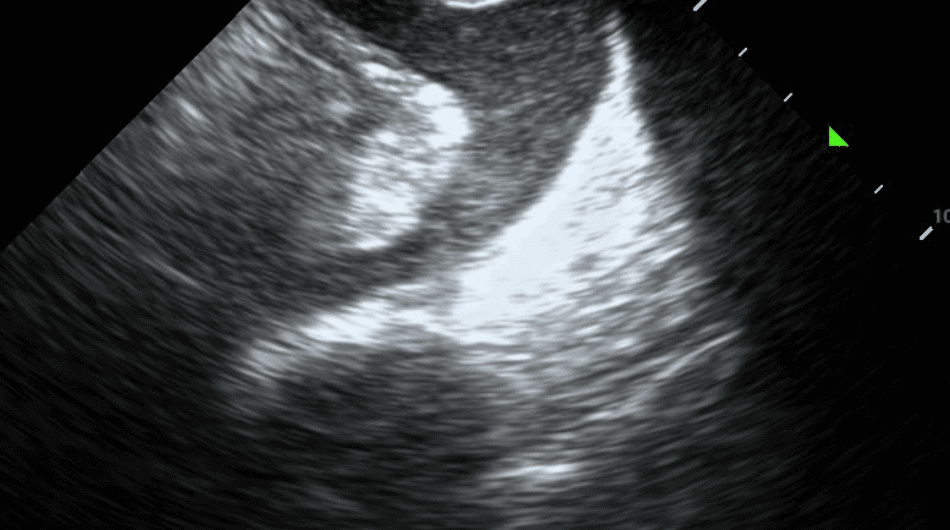

If a pleural effusion is present, there will be an anechoic (ie. black) space above the diaphragm. Please note that an anechoic space below the diaphragm represents ascites; not a pleural effusion. Two other other features will stand out to you. Firstly, you will see a “spine sign.” Normally, the spine cannot be visualized above the diaphragm since aerated lung scatters ultrasound beams before it can reach the spine. However, a pleural effusion will allow sound waves to be transmitted to the spine and you will see the spine clearly visible above the diaphragm.

Secondly, you will see a consolidated lung sitting in the effusion. Please refer to our post on consolidations to learn what consolidated lung looks like. If the effusion is large, the consolidated lung will appear to float in the effusion - resembling a jellyfish swimming in the ocean. This is referred to as the “jellyfish sign.”

Estimating the size of a pleural effusion can help determine if, when and where the effusion can be drained. Effusion size may be qualitatively classified as small, medium or large. If there is a “jellyfish sign,” the effusion is at least moderate to large in size.